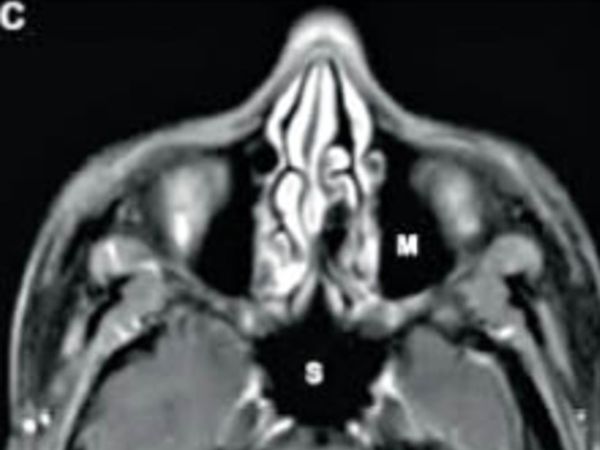

यह नॉर्मल स्कैन है। ब्लैक फंगस का संक्रमण नहीं है। सायनस में संक्रमण नहीं हाेने से वह काला दिख रहा है।